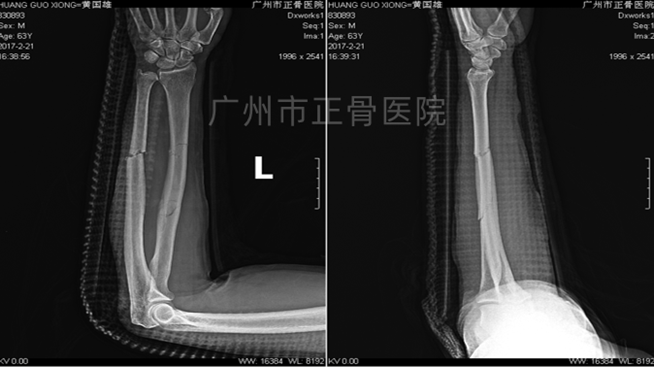

▲3天后复查见尺骨移位

▲手法调整后加石膏托固定